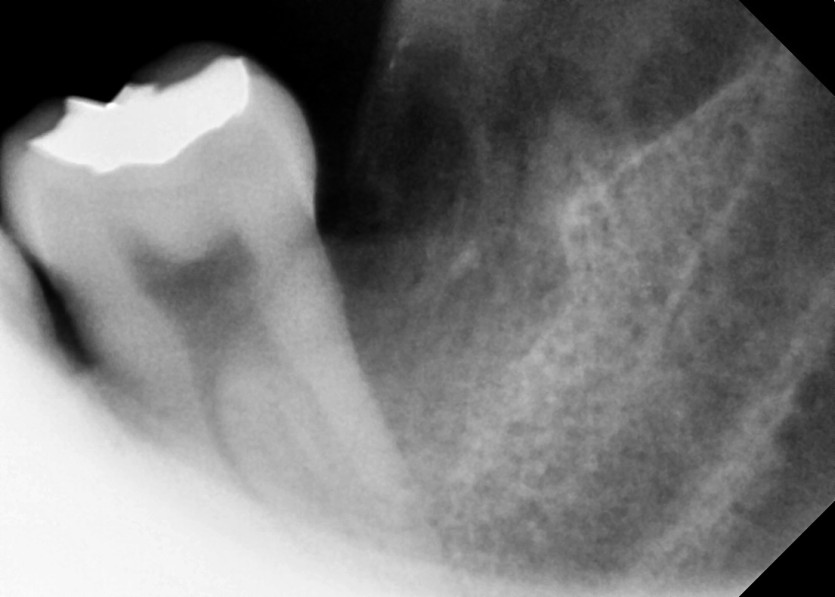

#28,38 사랑니 발치

구강외과 전문의가 당일 발치했습니다.